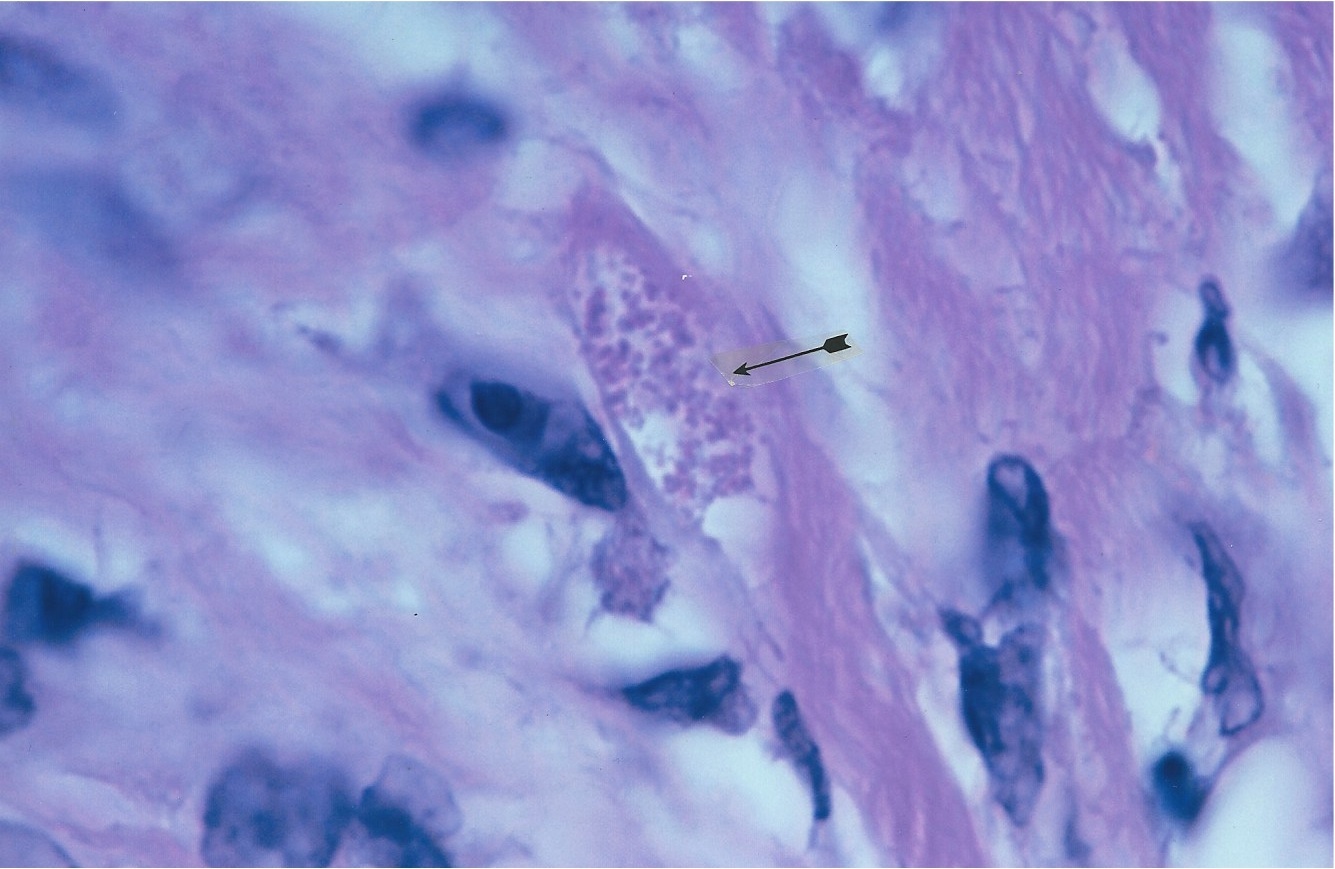

Figure 1. Enlarged lymph node from an AIDS case reported as “benign lymph node hyperplasia”. The straight arrow points to a

transparent Giant Russell body. Compare the size to red blood cells indicated by curved arrow. Hematoxylin-eosin stain, magnification x1000, in oil.

Figure 2. Same lymph node as Figure 1. Arrow points to a collection of large, balloon-like forms of Russell bodies. Fite (acid-fast) stain, x1000